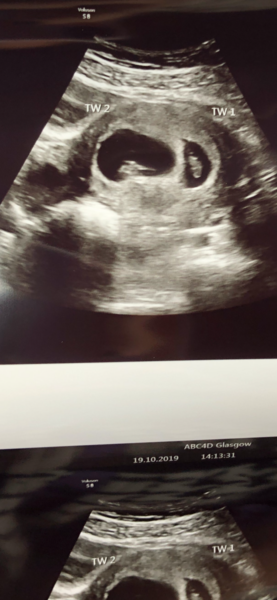

Robs20 · 19/10/2019 21:03

@Jemstar33 how did you get on today?

Jemstar33 · 19/10/2019 22:06

Hey @robs20 thanks for checking in. All was fine! Babies are 1.5cm long and hearts are beating away! Really think we work ourselves up by expecting the worst. I hope you’re feeling better soon. I found taking to the babies made me calm down (a bit) x

@Jemstar33 so glad all was ok! Just had mine and despite my worries both little beans are still in there!